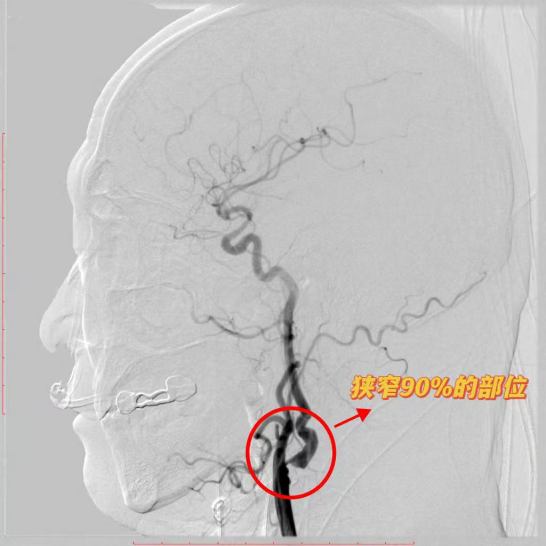

(图一:颈动脉内膜斑块切除术前患者堵塞部位)

据了解,春节后一周内,脑科团队先后攻克颈动脉内膜剥脱术、三叉神经微血管减压术、立体定向导航下小脑血肿穿刺引流术三大难关。其中,颈动脉内膜剥脱术针对颈动脉重度狭窄患者,通过显微技术剥离斑块,有效预防脑卒中;三叉神经微血管减压术为顽固性三叉神经痛患者解除“天下第一痛”;立体定向导航下小脑血肿穿刺引流术则精准清除颅内血肿,挽救脑出血患者生命。